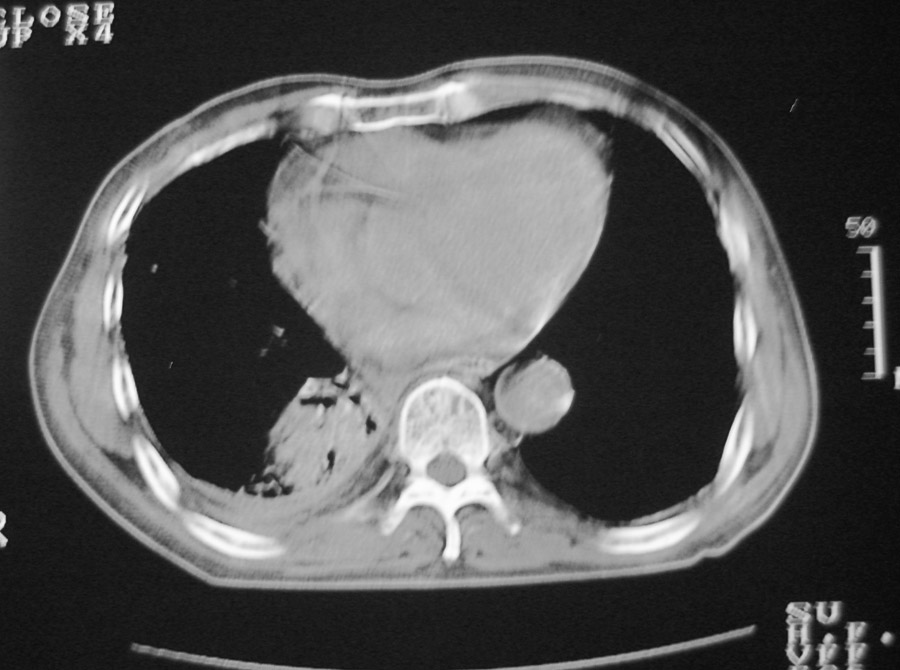

以下是引用hhcckk在2007-1-24 18:11:00的发言:[br]病灶周围胸膜反应比较明显,考虑炎症可能性大点,病人年龄较大,病灶成块状,肿瘤也不能排除,可可西里老师看片子的确很仔细,隔离肺暂时我觉得证据的说服力不大,上下层面显示条状影范围较长,可能是增厚的胸膜,可以做个增强鉴别一下

以下是引用天南地北在2007-1-24 18:00:00的发言:[br]1:右下肺内基底段类椭圆性肿快影:考虑1:右下球形肺炎2:右下肺隔离症,建议抗炎治疗后复查。[br]2:右肺及左下肺感染,右侧少量胸腔积液。